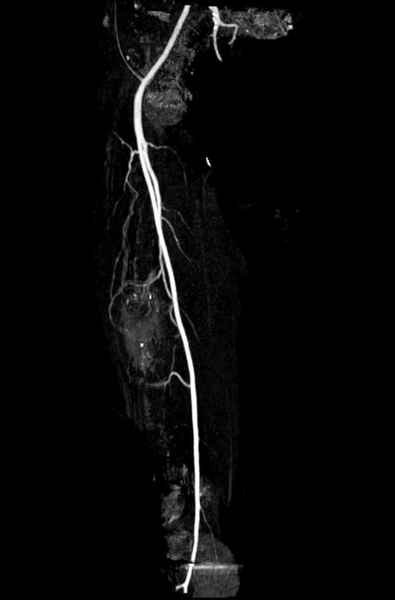

Для предупреждения кровотечения во время рассверливания, за день до операции провели эмболизацию сосудов питающий метастаз. http://radiology.rsnajnls.org/cgi/reprint/150/3/673.pdf (7-11, 12-15-16)